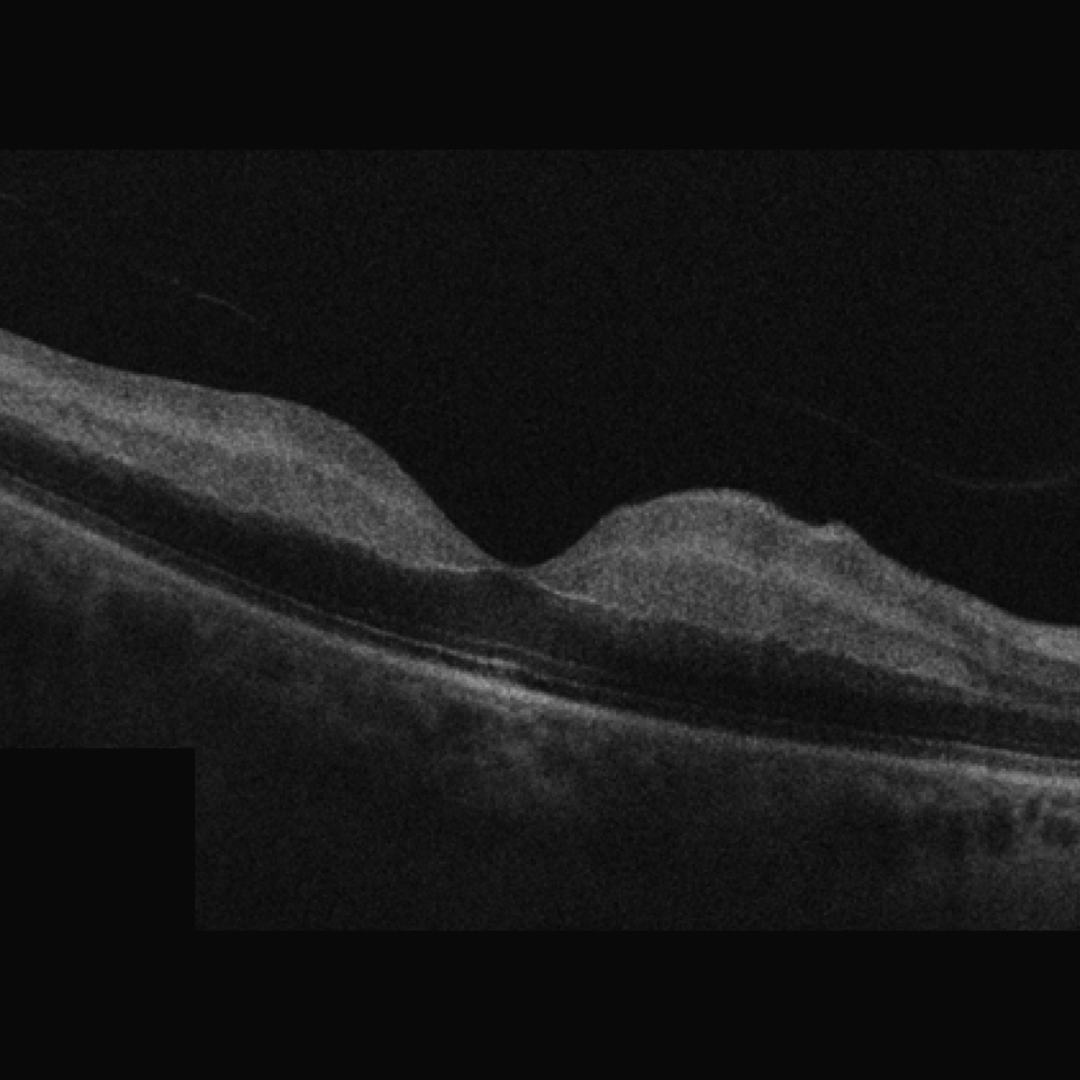

Retinal oedema, seen on OCT as a thickening of the inner retinal layers, is associated with acute retinal arterial occlusion.

Over time, a chronic arterial occlusion results in atrophy and loss of the inner retinal layers which can be detected with OCT imaging. Neovascularisation is very rare in all forms of retinal arterial occlusion.